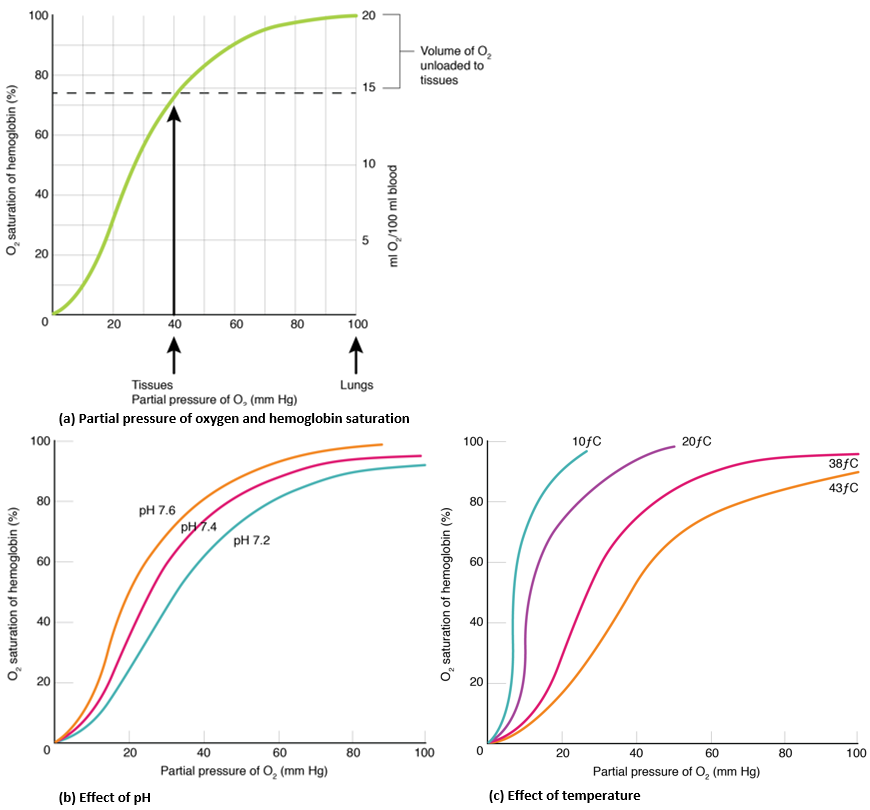

Binding of the first oxygen molecule causes a conformational change in hemoglobin that allows the second molecule of oxygen to bind more readily. As each molecule of oxygen is bound, it further facilitates the binding of the next molecule, until all four heme sites are occupied by oxygen. The opposite occurs as well: After the first oxygen molecule dissociates and is “dropped off” at the tissues, the next oxygen molecule dissociates more readily. When all four heme sites are occupied, the hemoglobin is said to be saturated. When one to three heme sites are occupied, the hemoglobin is said to be partially saturated. Therefore, when considering the blood as a whole, the percent of the available heme units that are bound to oxygen at a given time is called hemoglobin saturation. In a healthy individual with normal hemoglobin levels, hemoglobin saturation generally ranges from 95 percent to 99 percent.

The mechanisms behind the oxygen–hemoglobin saturation/dissociation curve also serve as automatic control mechanisms that regulate how much oxygen is delivered to different tissues throughout the body. This is important because some tissues have a higher metabolic rate than others. Highly active tissues, such as muscle, rapidly use oxygen to produce ATP, lowering the partial pressure of oxygen in the tissue fluid. The difference in partial pressure of oxygen in the muscle tissue and the capillaries becomes quite high. As a result, a greater number of oxygen molecules dissociate from hemoglobin and enter the tissues. The reverse is true of tissues, such as adipose (body fat), which have lower metabolic rates. Because less oxygen is used by these cells, the partial pressure of oxygen within such tissues remains relatively high, resulting in fewer oxygen molecules dissociating from hemoglobin and entering the tissue fluid.

Although venous blood is said to be deoxygenated, some oxygen is still bound to hemoglobin in its red blood cells. This provides an oxygen reserve that can be used when tissues suddenly demand more oxygen.

Factors other than partial pressure of oxygen also affect the oxygen–hemoglobin saturation/dissociation curve. For example, a higher temperature promotes hemoglobin and oxygen to dissociate faster, whereas a lower temperature inhibits dissociation (see Figure 20c). However, the human body tightly regulates temperature, so this factor may not affect gas exchange throughout the body. The exception to this is in highly active tissues, which may release a larger amount of energy than is given off as heat. As a result, oxygen readily dissociates from hemoglobin, which is a mechanism that helps to provide active tissues, such as muscles, with more oxygen.

The pH of the blood is another factor that influences the oxygen–hemoglobin saturation/dissociation curve (see Figure 20b). A lower, more acidic pH promotes oxygen dissociation from hemoglobin. In contrast, a higher, or more basic, pH inhibits oxygen dissociation from hemoglobin. The greater the amount of carbon dioxide in the blood, the more molecules that must be converted to carbonic acid, which in turn generates hydrogen ions and thus lowers blood pH. Furthermore, blood pH may become more acidic when certain byproducts of cell metabolism, such as lactic acid, carbonic acid, and carbon dioxide, are released into the bloodstream. As a result, in metabolically active tissues that create more metabolic acids, oxygen delivery is increased.